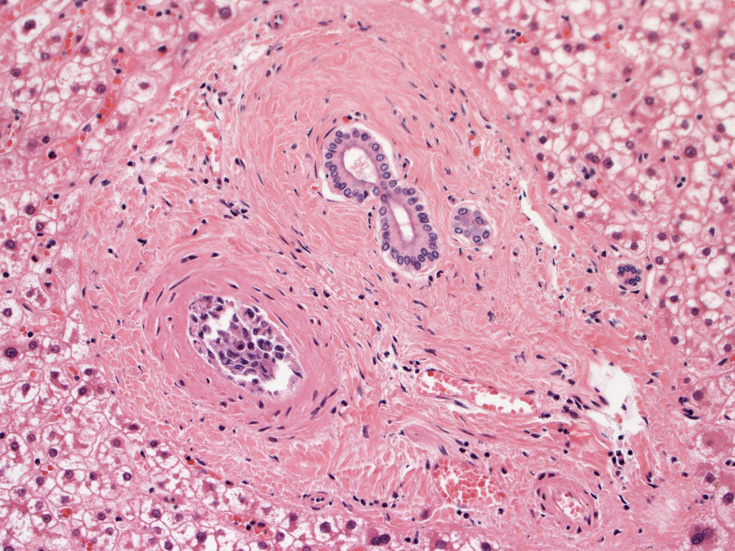

肺組織所見

血管内異常リンパ球増殖症例であるが、細胞はCD20陰性, CD79a陰性, CD3陰性である。BCR, TCR遺伝子再構成も認められなかった。(細胞量の関係もあるか?). EBER-ISHは周囲小型リンパ球に陽性所見を認めたが腫瘍細胞はEBER(-)であった。